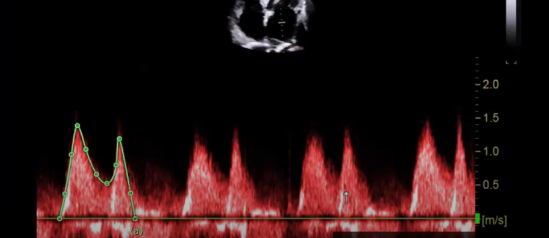

what is this measurement for

This measuring above the baseline for stenosis, this is our MV VTI

you want to Trace the E and A, a normal MV mean gradient is going to be less than five (if we see a very heavy calcified vale that is not opening well the CW is going to assessing for)